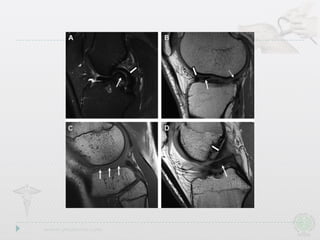

} MRI is the gold standard

of diagnosis

Imaging